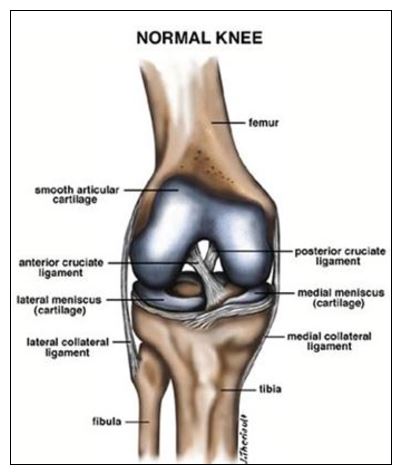

The ACL (anterior cruciate ligament) is part of a complicated network of ligaments that help stabilise and hold the knee. These structures are especially vulnerable to injury during sporting activity or as the result of direct impact.

ACL rupture is often associated with meniscal and medial ligament injury. This combination is known as a the “terrible triad” of knee injuries.